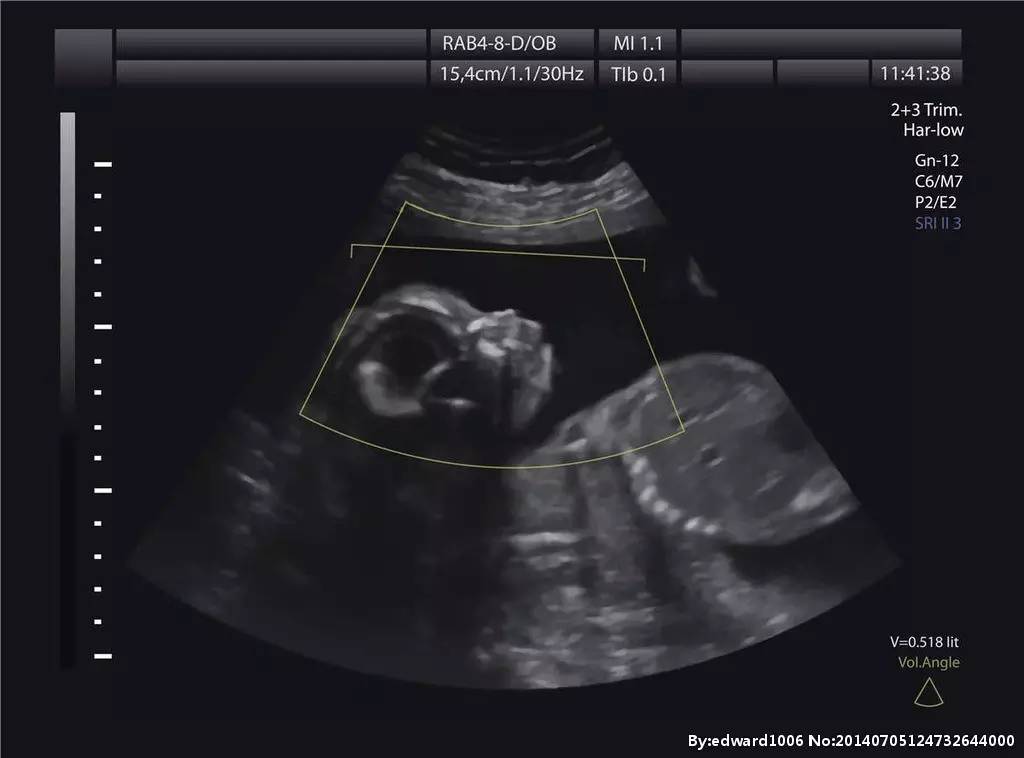

(B超图)

B超和彩超属于平面照片,三维、四维B超就是立体照片了。